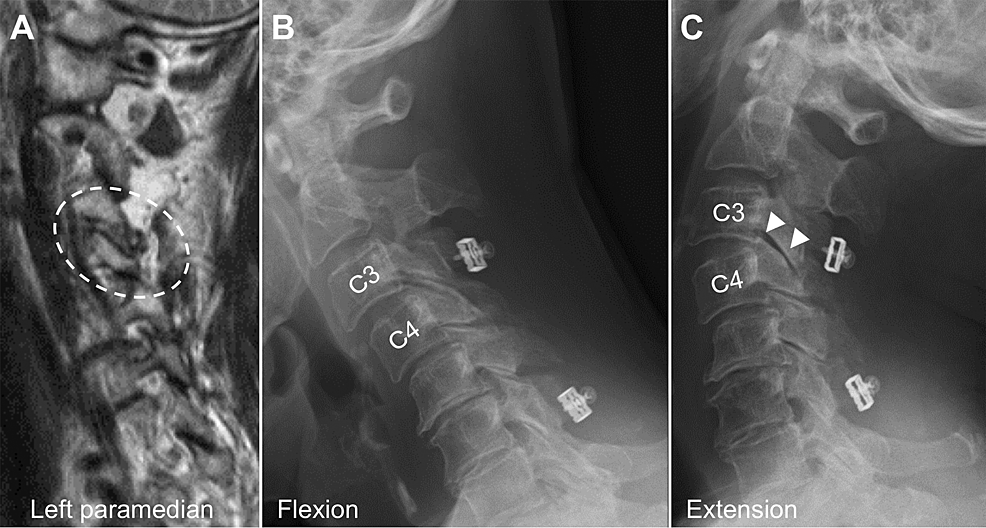

Bilateral Facet Dislocation Facet Joint Radiology Ct and mri are the leading imaging modalities for diagnosis of facet joint diseases. Without a fracture, the only way anterior. Facet dislocation refers to the anterior displacement of one vertebral body on another. Facet joint neoplasms like osteoid osteoma, plasmacytoma, tenosynovial giant cell tumor, and osteochondroma are best evaluated at ct or mri. The authors provide an overview of.. Facet Joint Radiology.